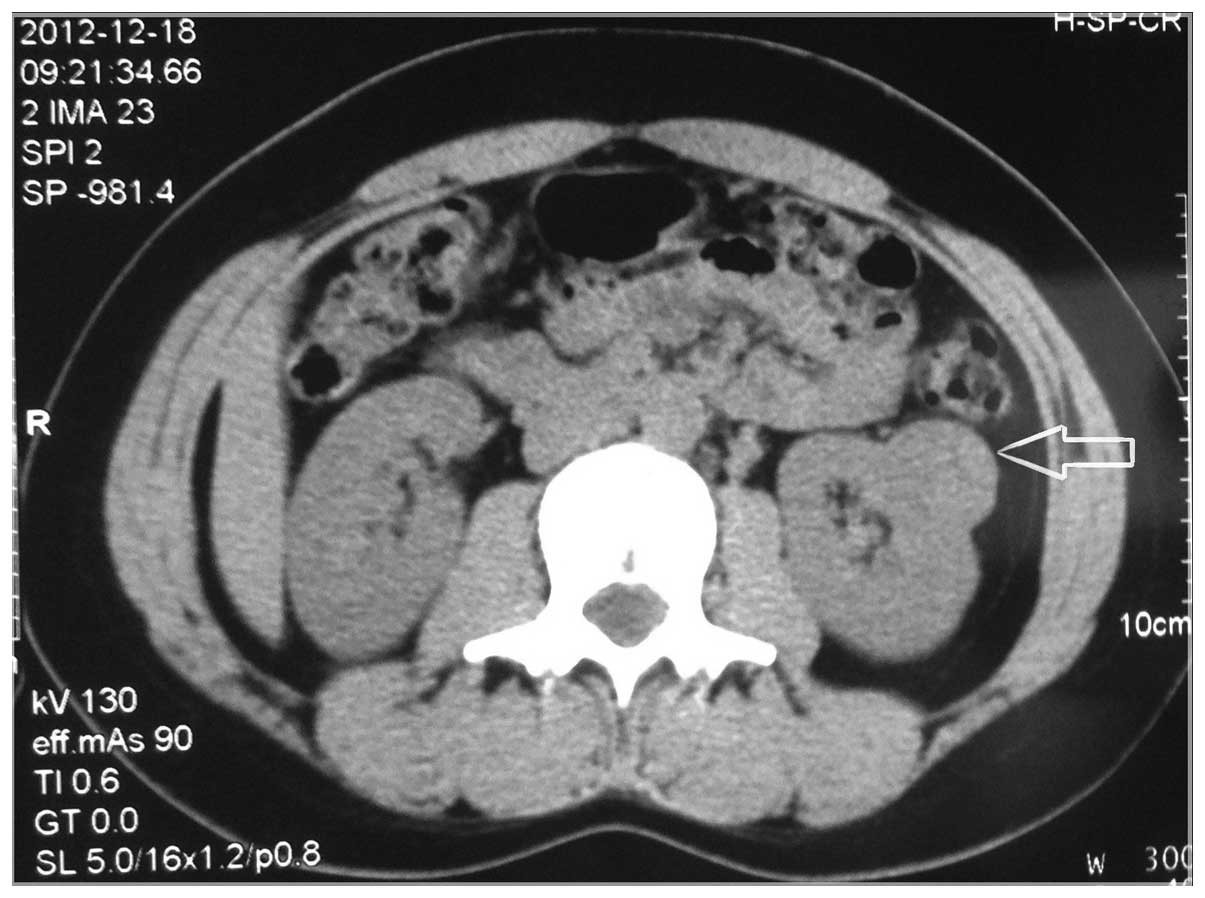

Clinical characteristics and pathology of thyroid‑like follicular carcinoma of the kidney: Report of 3 cases and a literature review

Thyroid‑like follicular carcinoma (TLFC) of the kidney is an extremely rare type of renal tumor, which has not been classified under a known subtype of renal cell carcinoma. It is histologically similar to the primary thyroid follicular carcinoma; however, the characteristics lack thyroid immunohistochemical markers. The aim of the present study was to illustrate the clinical characteristics of 3 new cases along with a review of the literature. The patients were compared with regards to gender, age, location and size of the tumor, imageology, morphology, immunohistochemistry and prognosis. According to the limited data, TLFC occurs mainly in young women and its clinical manifestations have no difference with other renal tumors. Its imageological features resemble a large spectrum of benign and malignant renal and extra‑renal conditions, which should be eliminated in the diagnostic process. Confirmed diagnosis depends on the examination of pathology and immunohistochemistry. Surgical ablation is the preferred therapeutic method. Currently, TLFC has a relatively good prognosis; however, this conclusion requires further cases and long‑term follow‑ups. Improving the understanding of TLFC can help avoid misdiagnosis and prevent inappropriate treatment.

Figure 1